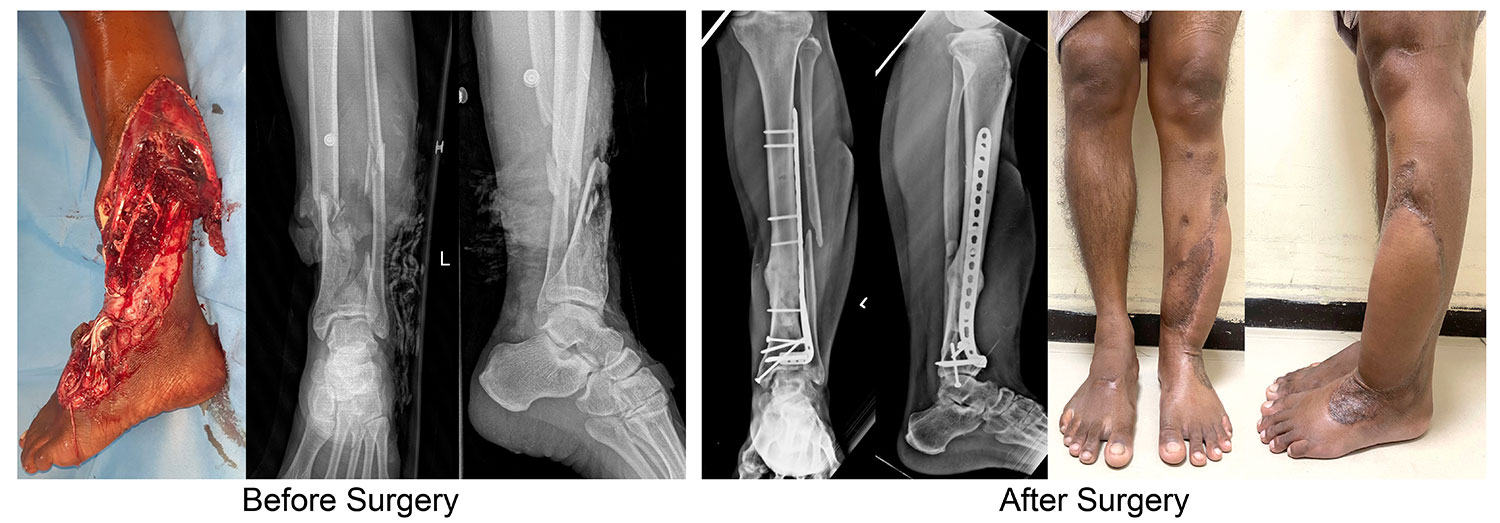

Severe open injuries of limbs are very common in the developing world due to high incidence of road traffic and work place accidents. The treatment for these are very variable in different countries and many limbs were not saved either because of lack of proper protocols or non-availability of expertise or insurance issues. We have done considerable research in this field of salvaging such limbs and also developed ‘GHOISS’ (Ganga Hospital Open Injury Severity Score) which gives very clear guidelines of when to salvage and also the timing and type of limb reconstruction. The indication and protocol for limb salvage are very different from the developed and developing countries and this area is a perfect example of why developed and developing world cannot have the same protocols and indications.

However amputation was a challenge in the developing world as it not only had a social stigma, but also seriously disadvantaged the patient due to life style of the developing countries. Further good quality prosthesis was not available in rural areas. These challenges led us to develop GHOISS (Ganga Hospital Open Injury Severity Score) which allowed us to have a clear objective method of assessing open injuries and also various innovations which allowed reduction of stages of reconstruction and cut down costs. This protocol is now followed very widely in developing countries which has allowed saving of amputation of many limbs.